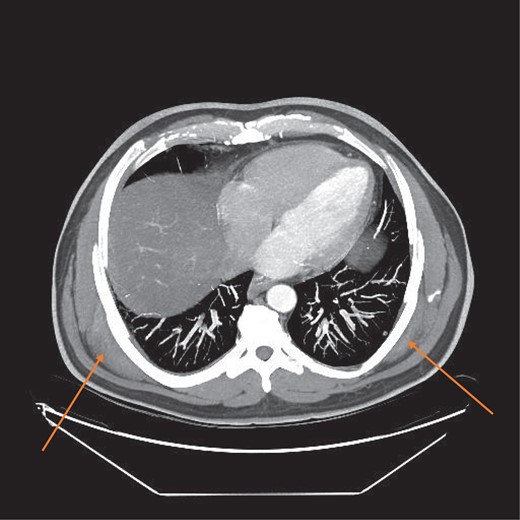

MRI confirmed the diagnosis and showed a second lesion on his left side, also at the infrascapular area (Figs 1–3). The patient had not complained of any symptoms to his left side or his left shoulder joint. After an extensive discussion with the patient and his family, we decided on a computerized tomography (CT) guided true cut biopsy to confirm the diagnosis (Fig. 4).

MRI axial view showing bilateral elasto fibromas (orange arrows) on the posterior rib cage.